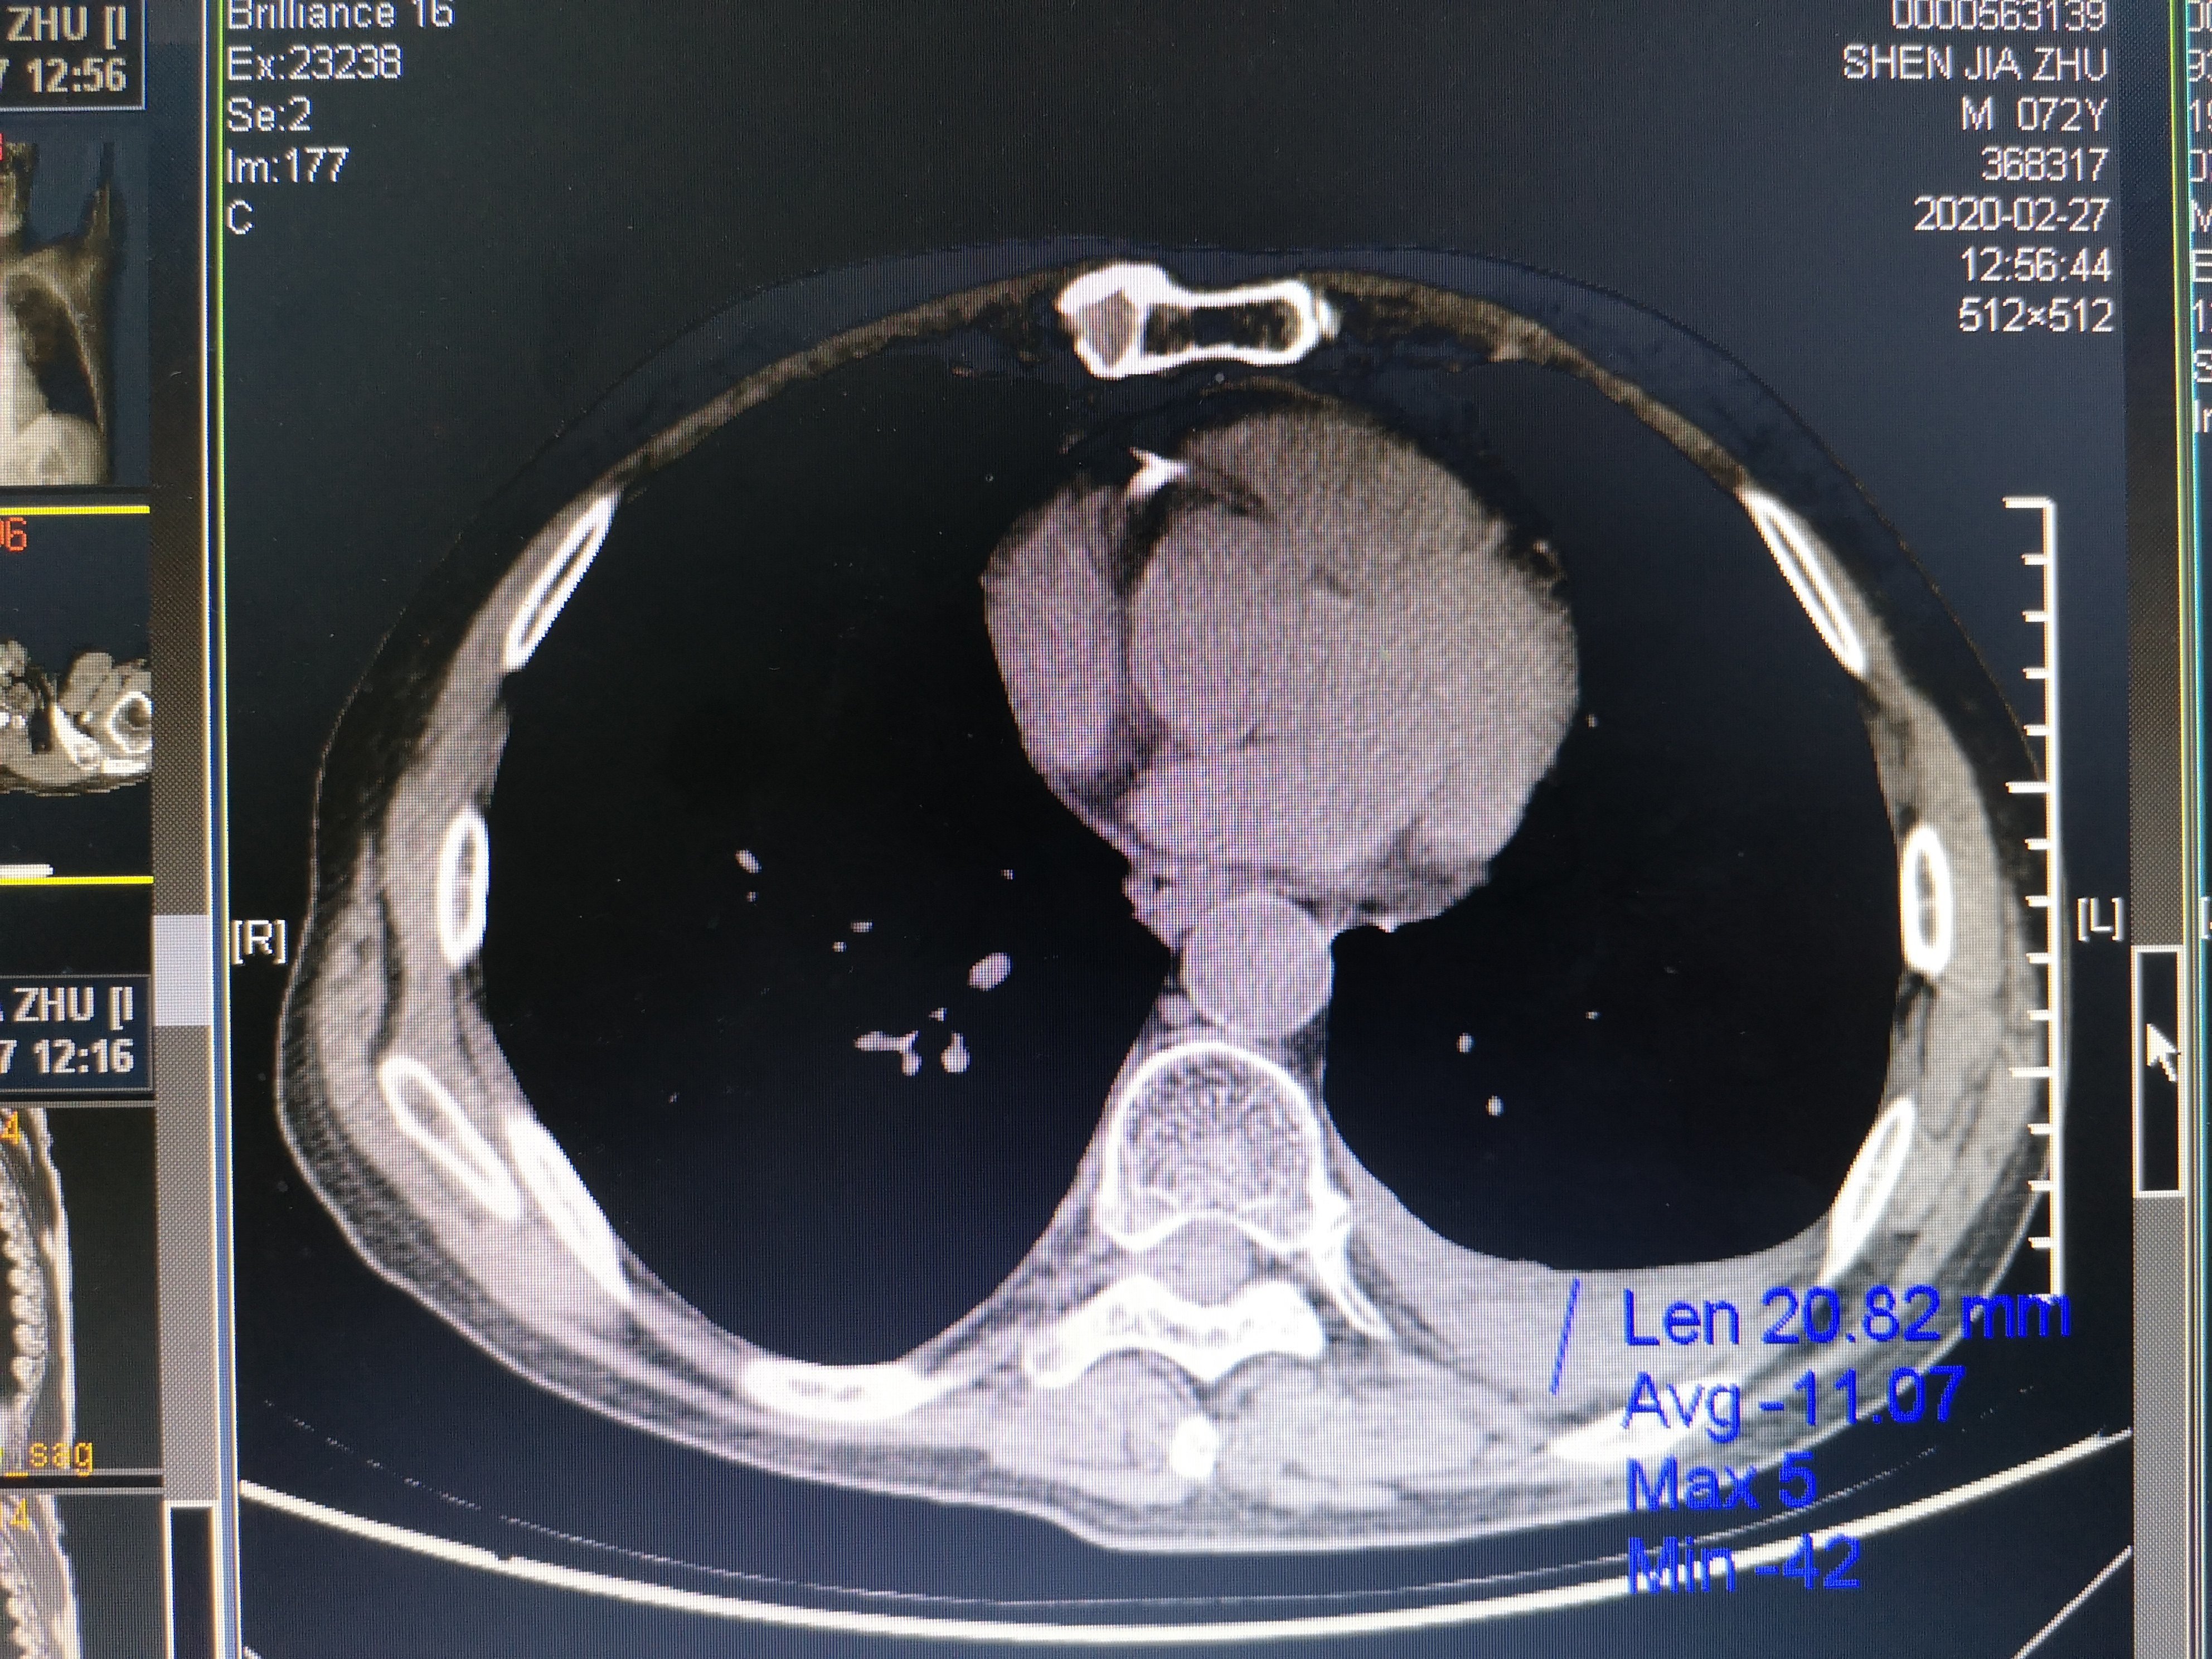

然后这一次这个病号来到我们医院给他做了一个磁共振和CT我们来看下图

从上面这张CT图我们可以看出这个患者左侧有胸腔积液,就是我上面标注的地方。这说明他的肺已经转移了!